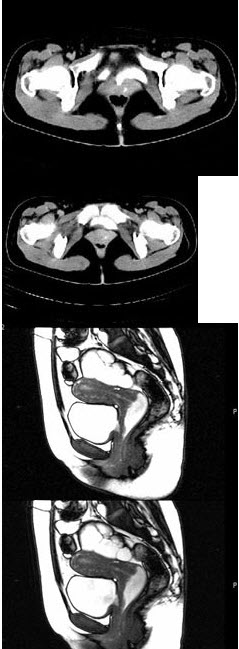

35、多项选择题

女,28岁,阴道有异常液体流下,CT和MRI扫描如图,下列说诊断正确的是()

A.CT增强示造影剂由膀胱进入阴道

B.MRI的T2加权像示宫颈阴道内有大片状高信号影

C.膀胱后下缘可见鸟嘴状突起

D.考虑为左侧输尿管异位开口

E.考虑为膀胱阴道瘘